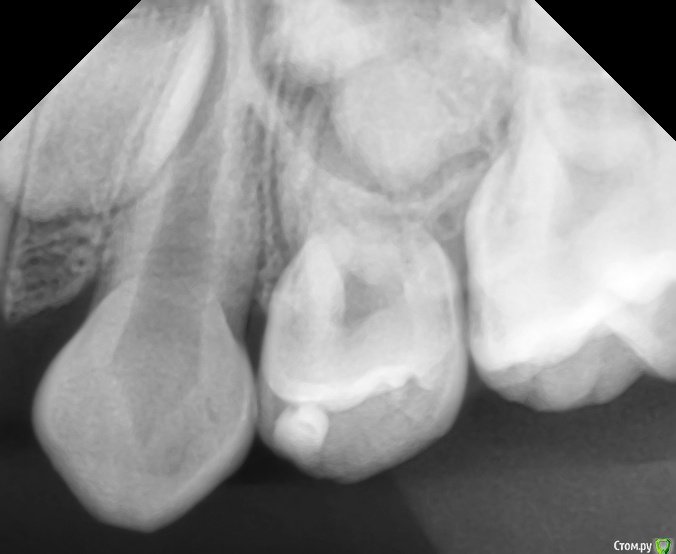

CRAZYDUCK Опубликовано 20 мая, 2018 Автор Поделиться Опубликовано 20 мая, 2018 Вовремя замеченный кариес не успеет превратиться в пульпит . Поверхностный кариес контактных поверхностей 6.5 и 6.4 зубов, подтверждённый RVG исследованием . Серёже 3,5 года , но он большой молодец , продолжительность 45 минут ( анестезия, коффердам , преп турбиной и рондофлекс , пломбирование и полировка. 1 Ссылка на комментарий